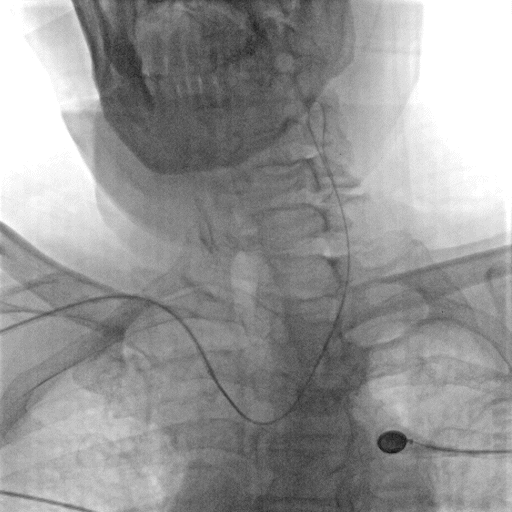

影像信息

主动脉弓上血管多发斑块形成。

左侧锁骨下动脉显示左侧椎动脉开口重度狭窄,狭窄率85%,供血至PICA。

双侧颈动脉造影提示双侧颈内动脉多发斑块形成,远端血管显影良好。

右侧锁骨下动脉造影提示右侧椎动脉主供血,开口无狭窄,椎动脉V4段局限性重度狭窄,狭窄率 80%,远端基底动脉及分支血管显影良好。